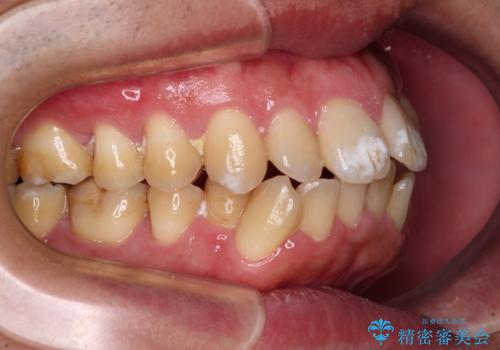

- 口が閉じられないとのことで来院された患者様です。

顎先に力を入れないと唇が閉じきれない口元であったので、上下左右の第一小臼歯4本を抜歯して、ワイヤー装置にて矯正治療を行うこととしました。